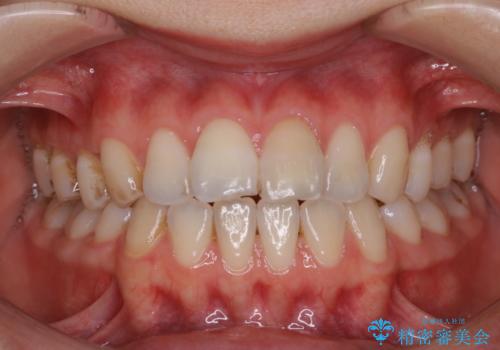

1年ぶりにPMTCで歯の着色落とし

- しばらく歯科医院へ行けなかったため、しっかり着色や汚れを落として欲しいとのことで来院されました。全体的に着色や歯石が付着していたためPMTC60分コースを行いました。

ご自身でのセルフケアだけで着色を落とそうとすると、逆に歯を傷つけてしまったり、的確に汚れを取りきれないことがあります。また、日常生活で着色しやすい飲食物を避けたりすることはストレスに感じてしまったり、あまり現実的ではありません。

定期的に歯科医院にて、適切な処置を行うことで、健康的なお口の状態を維持することにつながります。